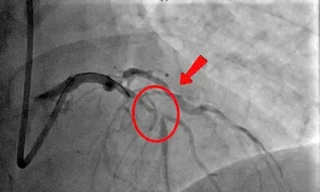

TPO - Đang đi khám vì cơn đau ngực kéo dài, người đàn ông 46 tuổi bất ngờ lên cơn nhồi máu cơ tim cấp ngay tại bệnh viện. Các bác sĩ đã kịp thời chẩn đoán, can thiệp giúp bệnh nhân thoát chết trong gang tấc.